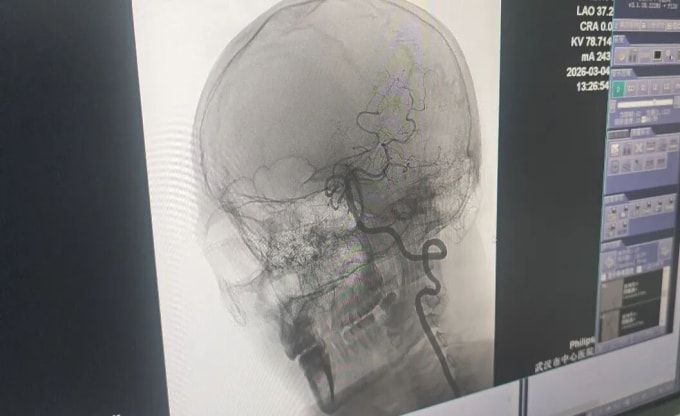

Tại bệnh viện, các bác sĩ thần kinh chẩn đoán bệnh nhân tắc nghẽn mạch máu lớn cấp tính và chỉ định truyền thuốc tiêu sợi huyết qua tĩnh mạch. Tuy nhiên, chỉ nửa giờ sau, tình trạng anh Vương chuyển biến xấu. Anh rơi vào hôn mê sâu, đồng tử trái giãn, mất phản xạ ánh sáng, liệt hoàn toàn nửa người trái kèm liệt mặt, lưỡi và mất khả năng ngôn ngữ. Bác sĩ tiến hành chụp mạch máu và phát hiện vết rách ở lớp nội mạc động mạch đốt sống gây rối loạn huyết động nghiêm trọng, hình thành cục máu đông làm tắc mạch. Bác sĩ Hùng Vĩ, Trưởng khoa Thần kinh, giải thích rằng phần mô lộ ra từ lớp nội mạc tổn thương đã kích thích tạo huyết khối nhanh chóng, dẫn đến bế tắc hoàn toàn lưu lượng máu.

Êkíp cấp cứu lập tức chuyển người bệnh đến phòng can thiệp mạch. Nhận thấy động mạch đốt sống chưa tắc nghẽn hoàn toàn, các chuyên gia quyết định thực hiện thêm phương pháp tiêu sợi huyết đường động mạch. Sự kết hợp đồng bộ này đã tái thông dòng máu chính xác, cứu sống bệnh nhân.